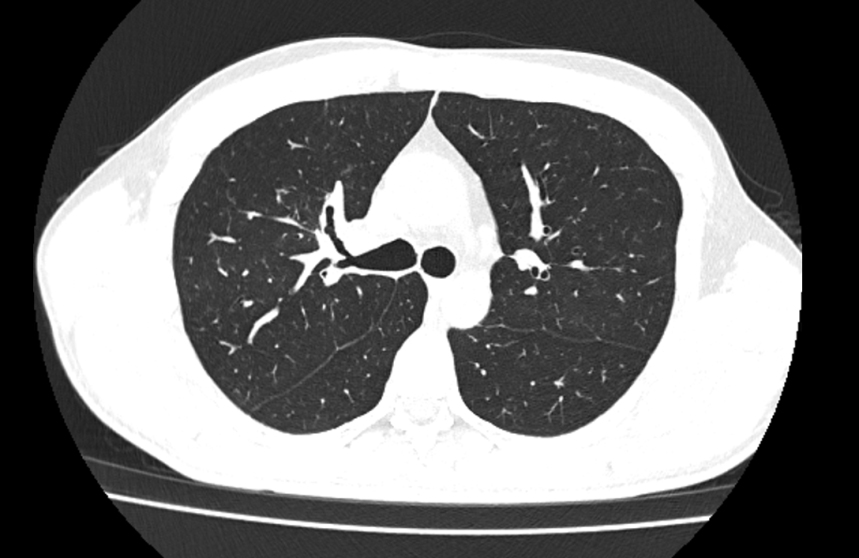

2、胸部CT检查:

(1)两肺多发支扩并感染,部分管腔内粘液栓形成,待排ABPA,请结合临床;

(2)房间隔区域金属致密影,拟术后改变;

(3)两侧肺门、纵隔多发小-稍大淋巴结,考虑反应性增生。